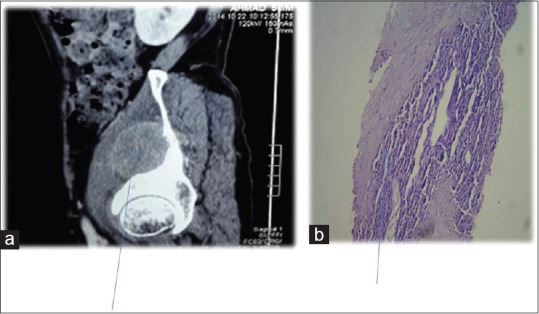

Further evaluation was carried out with imaging of chest and abdomen, along with imaging of referable sites. Contrast-enhanced computed tomography (CECT) chest and abdomen was carried out in all patients, revealing right hilar mass in 66% of patients, left hilar mass in 22%-of patients, and 12%-had right peripheral lung mass. Superior vena cava (SVC) partial or complete occlusion was seen in 33%; right-sided plural effusion, ascites, and liver metastasis was seen in 11%-each [Figures [Figures11 and and2].2]. Bronchoscopy revealed intrabronchial pathology and clinched the diagnosis in 88% of patients; rest of patients needed computed tomography (CT)-guided biopsy of lung for getting histological diagnosis. Lung biopsy was positive for napsin, cytokeratin (CK) 5/6, and negative for synaptophysin and thyroid transcription factor 1 [Figure 3]. Bone scan was positive in two patients with one uptake in iliac bone and other in Tibia [Figure 4 of X-ray Tibia]. CECT of muscle metastasis sites was done and biopsy was carried out in each patient [Figure 5]. Distribution of metastasis was unique, 66%-patients had pelvic skeletal muscle involvement, 22%-had thigh muscle, and 11%-had lower paraspinal muscle metastasis.

| Figure 2:Contrast-enhanced computed tomography showing (a) huge lung mass with necrosis (b) multiple liver metastases

| Figure 5:Contrast-enhanced computed tomography showing (a) Iliacus muscle involvement (b) biopsy of same muscle revealing squamous cell carcinoma metastases